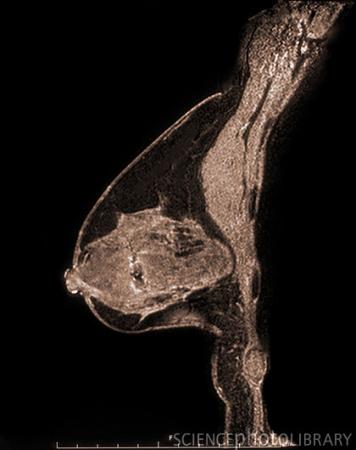

乳腺癌抑癌基因或因缺氧而沉默

前沿医学资讯网据悉,根据2011年8月发表在《Molecular and Cellular Biology》杂志的一篇论文,低氧可以使BRCA1肿瘤抑制基因沉默,并可促进癌症的进展,沉默这个特殊的基因是乳腺癌恶化的步骤之一。这项研究可能最终会导致重新激活这个和其他的肿瘤抑制基因的方法,以阻止癌症,通讯作者耶鲁大学的Peter Glazer说。